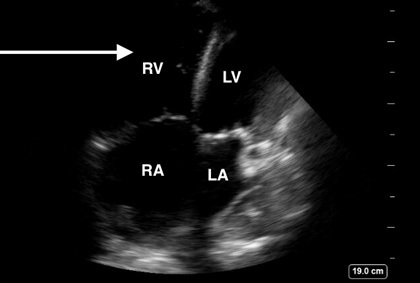

Echocardiography cannot be reliably used to diagnose PE; however, it can be used to assess for right ventricular (RV) dysfunction, which can be indicative of right heart strain from PE in patients with high suspicion.34 Point-of-care ultrasound frequently is used in the ED to evaluate for RV strain. Features such as the abnormal septal motion (D-sign), right ventricular hypokinesis (McConnell’s sign), and increased RV:LV ratio all have very low sensitivity but high specificity for PE in patients with concern for VTE.35 Additionally, a free-floating thrombus may be visualized in the right atrium or ventricle known as a clot-in-transit, which carries a high mortality.36 Evidence of right heart dysfunction or visualized thrombus can be used to guide empiric treatment in patients with high likelihood of PE who are too unstable to undergo additional imaging. (See Figures 2 and 3.)

Figure 2. Right Ventricle Dilation Secondary to Increased Right-Sided Heart Pressures |

Point-of-care ultrasound image demonstrating an apical four chamber view with RV dilation (white arrow) secondary to increased right-sided heart pressures |

Image courtesy of Daniel Migliaccio, MD. |